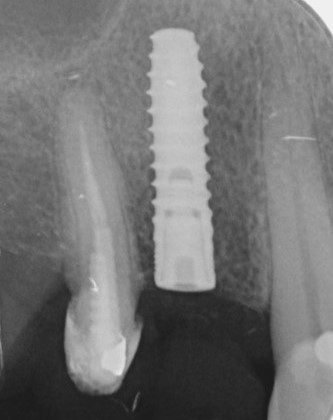

X-ray control image after the implantation. The implant was inserted as planned.